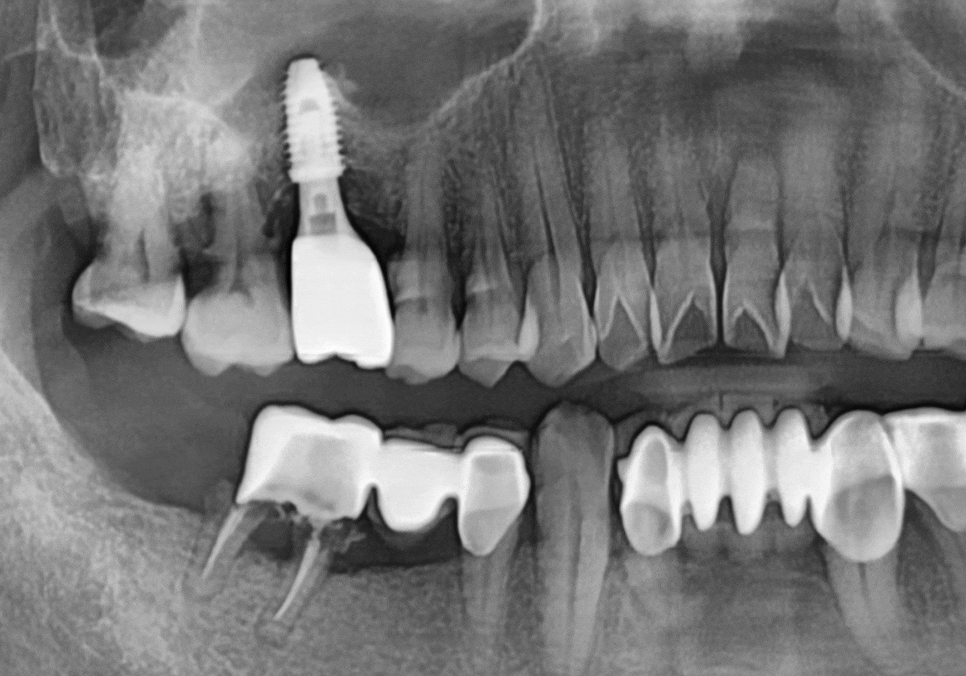

우선 오래된 브릿지를 조심스럽게 제거한 뒤

이미 제 기능을 잃고 뿌리만 남은

#46번 치아는

발치를 진행하기로 결정했습니다.

그 대신 오래전부터 치아가 상실되어

공간이 비어있던 #45번과 #47번 자리에는

튼튼한 임플란트를 심어

새로운 뿌리를 만들어드렸죠.

아래쪽 임플란트(#45~47)는 다행히 뼈가

아주 튼튼한 상태라

별도의 뼈이식 없이 진행했습니다.

한 달 뒤, 지르코니아 보철물까지

완벽하게 완성해 드렸죠.

상악동 거상술을 함께 했던 위쪽 치아는

조금 더 여유를 두었습니다.

4개월 뒤에 튼튼하게 자리 잡은 것을 확인하고

보철물을 올려 마무리해 드렸습니다.